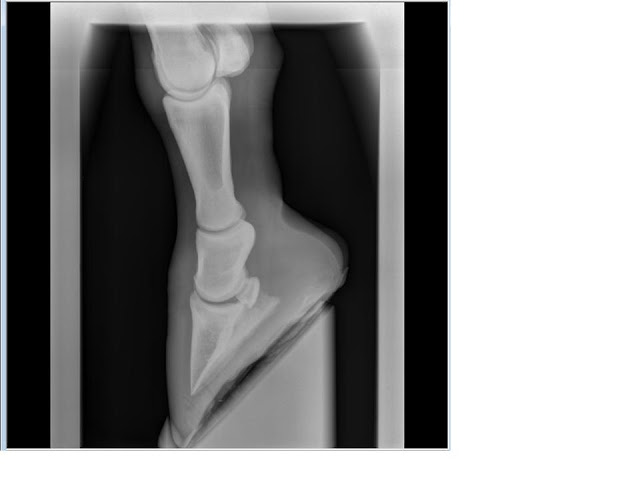

heeft er al iemand iedeeen/commentaar op de xrays? Ik heb er zelf weinig ervaring mee....